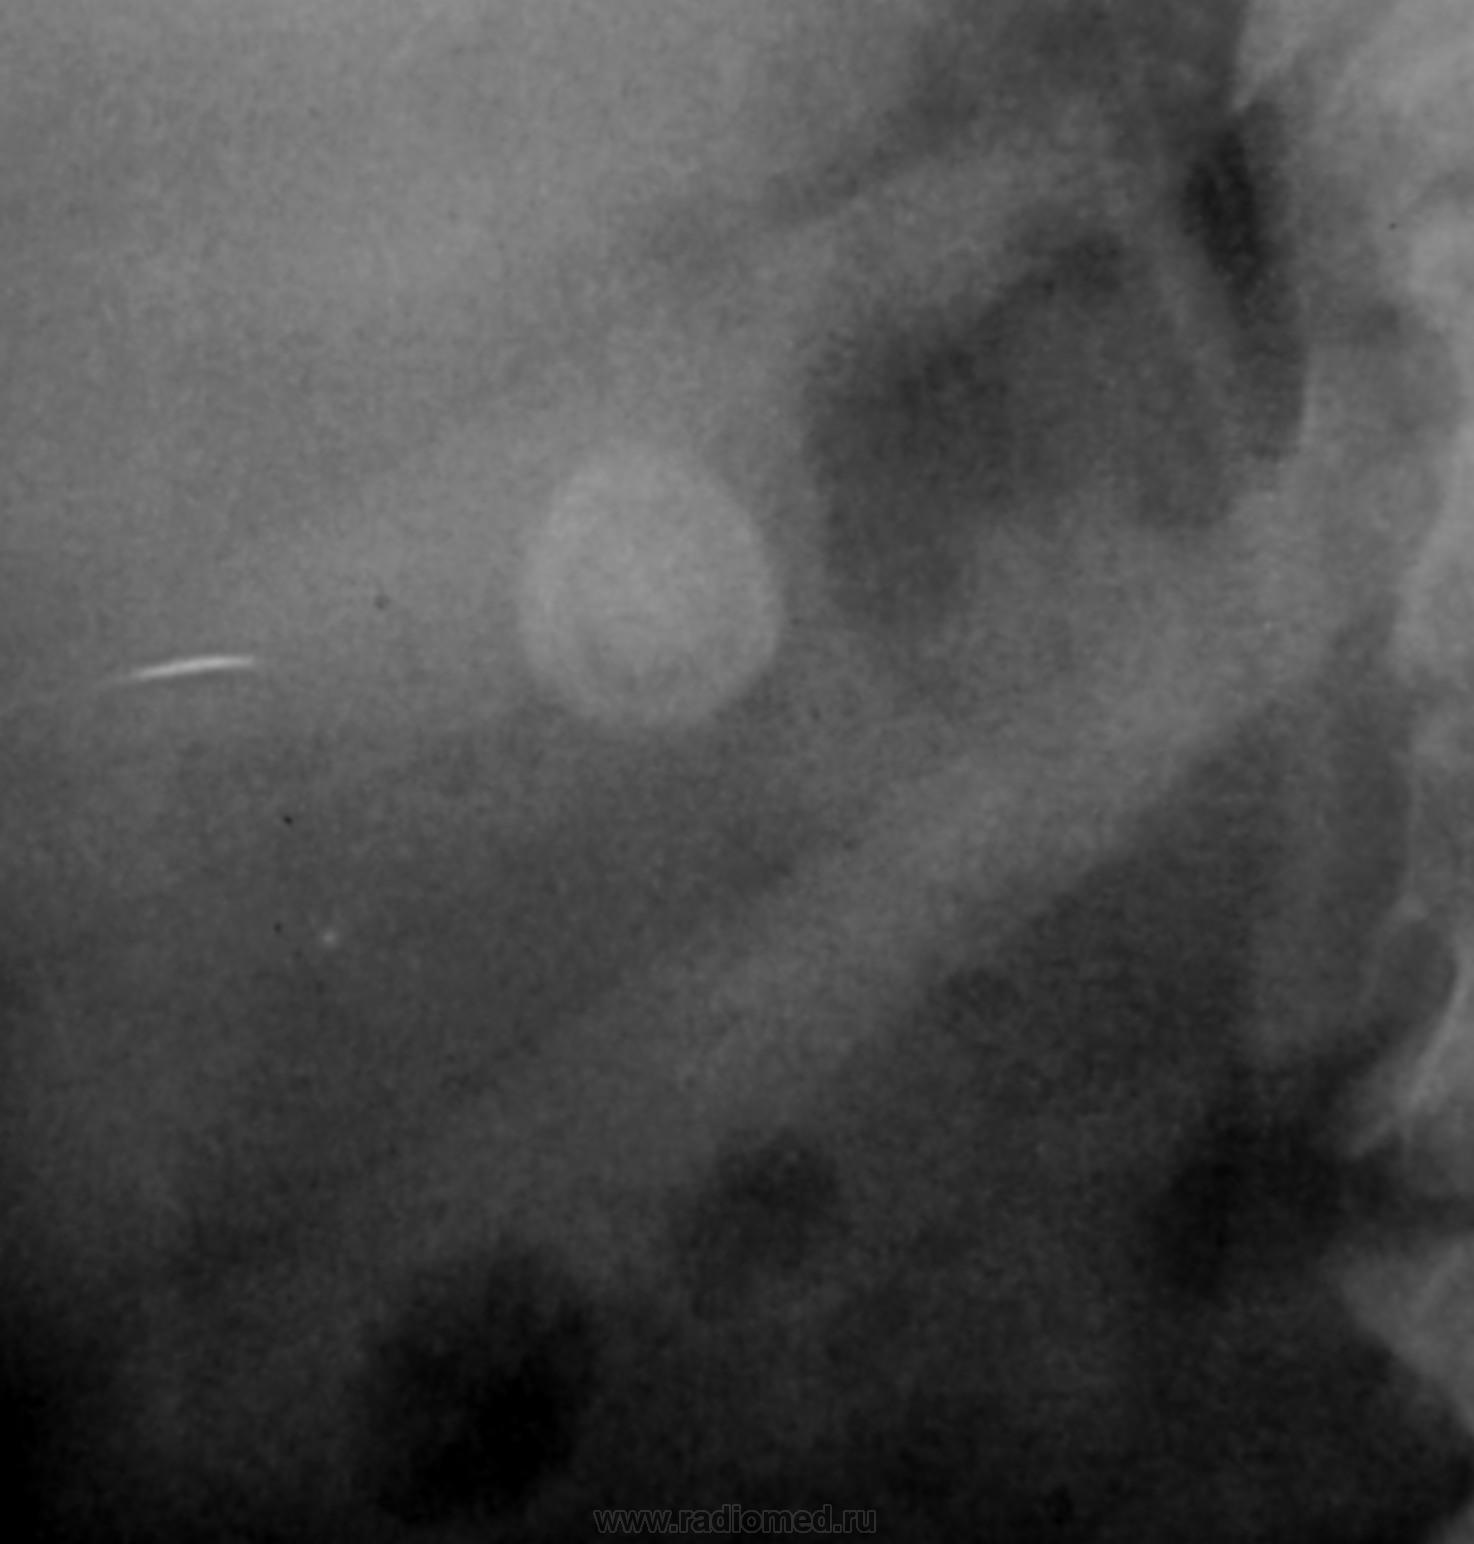

На мой взгляд дополнительная интенсивная тень лежит за контуром почки. В проекции Желчного пузыря. Так что желчекаменная болезнь? Рекомендованно УЗИ печени и желчного пузыря.

Да с камнем желчного то все понятно...но вот тень в проекции н\трети правого мочеточника ....весьма необычна...вопрос - куда ее "пристроить"?))))

Я не про "утверждаю", Боже спаси, для мочеточника тень очень больших размеров, хотя расположена вдоль его проекционной оси, но здесь же проекция крупных сосудов, стенты сейчас могут быть всякими разными, а потом-в малом тазу не только у женщин, но и мужчин хватает всякого, что может обызвествляться. А верхняя тень-типично для желчного пузыря.

Да, камешек для желчного типичный.

А тень в дистальной трети мочеточника действительно "фердиперсовая"...

Мне кажется, что тень в проекции н/3 правого мочеточника не меняет своей интенсивности на ОМПС и экскреторных урограммах. Отсроченный снимок просится и рентгенография малого таза в косых проекциях. Возможно, это НЕЧТО сдавливает н/3 правого мочеточника извне.